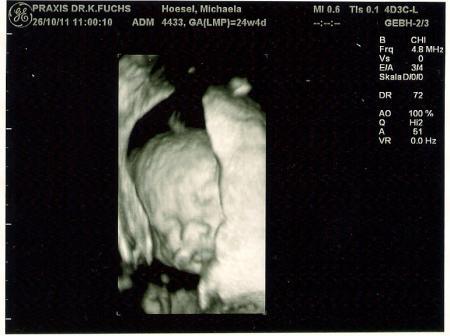

Und das schönste, wie ich finde, zum schluß. Eins vom Gesicht in 3D. Die nase vom Papa, da meine eher klein und zierlich ist und die des Papa etwas in die Breite geht. der Mund scheint von mir zu sein. Hat auch etwas tolles.

Oh wie goldig :) das 3D bild ist ja mal mega süß!